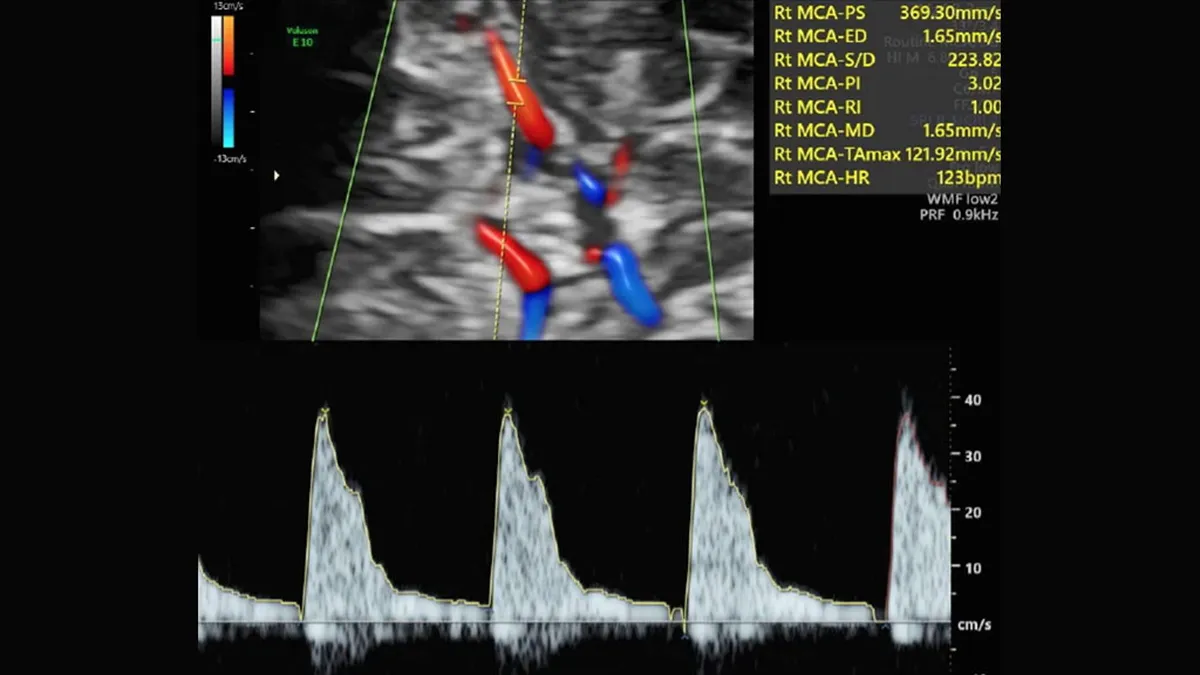

Una prueba con ecografía Doppler que mide la circulación de la sangre por el cordón umbilical y el cerebro, denominada ratio cerebro-placentario (o RCP), puede detectar la insuficiencia placentaria. Hasta ahora, esta prueba solo se realizaba en embarazos con problemas, en casos muy indicados. Desde hace más de 10 años ha existido un debate en el mundo científico sobre si había que medir el RCP en todas las embarazadas o era un gasto de recursos innecesario. Si la prueba Doppler se llevara a cabo en todos los embarazos, tal vez serviría para mejorar la detección de bebés con riesgo de complicaciones por insuficiencia placentaria. Pero también existiría el riesgo de que la prueba no mejorase nada y, en cambio, solo generase más gasto y angustia en las madres.

En el estudio RATIO37 han participado durante 6 años más de 11.500 mujeres con embarazos de bajo riesgo. En la ecografía de las 36 semanas se midió el RCP en todas las mujeres, pero las participantes fueron divididas al azar en dos grupos. En unas, la prueba se utilizaba para cambiar el manejo de la gestación y, en caso de salir alterada, se proponía a la mujer una inducción precoz del parto al llegar al término. En las otras, el resultado de la prueba no se comunicaba y se manejaba el embarazo según los protocolos vigentes. El estudio comparó los números de casos de muerte del bebé y de complicaciones neonatales graves (que incluían, entre otros, problemas neurológicos, intestinales, cardíacos, renales o respiratorios, con una estancia en la UCI de 10 días o más) que se producían en cada grupo.